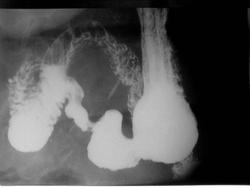

Деформация части 12-ти перстной кишки, скорее всего рубцовая

Аномалия ДПК. Ретрогастральное положение.

девект наполнения по большой кривизне в антральном отделе, на серии снимков, вроде присутствует, рельеф слизистой деформирован. ЭГДС делали?

рак наверное!

Думаю, да.

По малой кривизне перистальтика прослеживалась, а по большой - застывшая картина.

На мой взгляд, за что - это понятно. За неровность контура. Контур желудка при тугом заполнении барием должен быть ровным. А перистальтическая волна не может быть маленького размера (0,5 - 1,0 см). У меня вопрос был: где конкретно на снимках наиболее вероятен симптом ниши язвы, найденной на ФГС. Так как увиденная мной ниша на первом снимке бесследно исчезла на последнем снимке, я прошу помочь мне разобраться. Если сочтете нужным, конечно, коллеги. (Опыт по желудкам у меня небольшой).

[/quote]Дмирий, как это ни печально, но ниши я не нашла, хоть и очень старалась. Может, она фибрином прикрыта.

так там стенка инфильтрирована, основные изменения по большой кривизне просто.

на первом снимке нет тугого наполнения, поэтому это может и не ниша, на последнем я бы сказал депо конраста есть, просто на контур не всегда возможно вывести